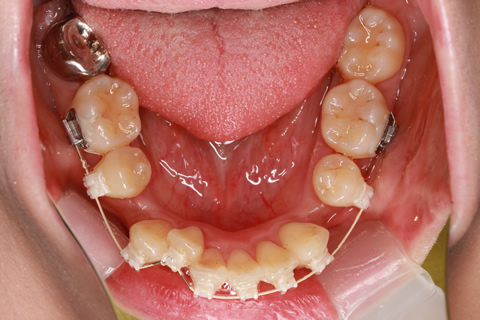

治療前

治療中(開始直後)

治療中(開始半年後)

治療後

- 年齢・性別

- 25歳女性

- 治療期間

- 2年0ヶ月

- 抜歯

- 上下4番抜歯

- 治療費

- 110万円

- 治療内容

- 施術の副作用(リスク)

- 表側矯正と比較して、力学的な操作性が複雑なため、ボーイングエフェクトを起こしやすい。